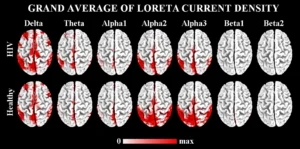

Il metodo sviluppato dai ricercatori si basa sulla registrazione dell’attività cerebrale tramite encefalografia. I dati raccolti vengono successivamente analizzati con una tecnica chiamata LORETA (Low Resolution Brain Electromagnetic Tomography), che consente di ottenere misurazioni quantitative del tracciato cerebrale.

Parallelamente all’analisi neurologica vengono effettuati anche test psicometrici, che permettono di valutare eventuali cambiamenti cognitivi nel tempo. Il monitoraggio avviene in diverse fasi: prima dell’inizio della terapia farmacologica, e successivamente dopo uno, due e cinque mesi di trattamento. In questo modo i ricercatori possono osservare se le variazioni cliniche del paziente sono accompagnate anche da modifiche nell’attività cerebrale.

Grazie alla raccolta e all’elaborazione di numerosi dati, il gruppo di ricerca ha sviluppato anche uno strumento statistico basato su un algoritmo matematico. Questo sistema consente di analizzare il tracciato cerebrale e determinare se l’attività neurologica del paziente risulti alterata oppure nella norma. I risultati ottenuti permettono quindi di valutare l’efficacia delle terapie e di adattare il trattamento alle caratteristiche specifiche di ogni individuo.

Leggi di Più..Sorgenti Corticali Anomale dei Ritmi

Lo studio propone un metodo basato sullo Z-score per individuare...